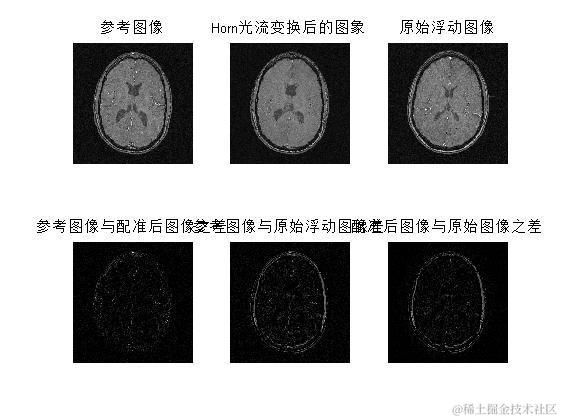

三、运行结果

在这里插入图片描述